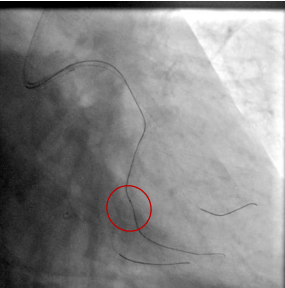

OM2处理时,当导丝通过病变后,其他器械无法通过病变时,选择0.7mm极小球囊顺利通过并预扩病变。

当血管内超声发现360度环形钙化,非顺应性球囊无法充分扩张病变时,选择2.5×12mm的冲击波球囊4atm即将病变充分扩张。